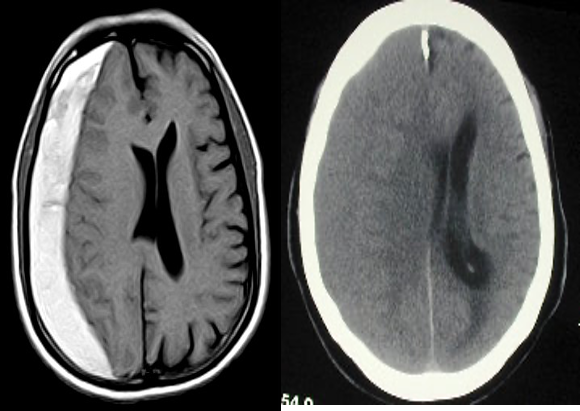

Subacute subdural hematoma

T1- Hyper in subacute

T2 - Hypo - Hyperintense also